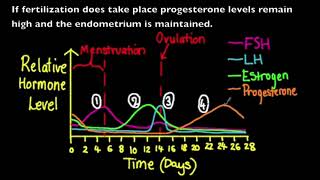

44. Animal Reproduction

Animal Reproduction

Menstrual Cycle (Mnemonic)